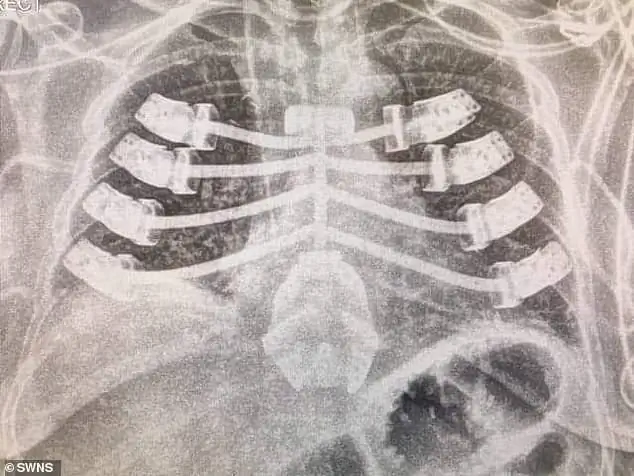

3D-печать зарекомендовала себя как полезный инструмент для создания медицинских решений для конкретных пациентов благодаря свободе дизайна, предлагаемой технологией. Во второй половине 2019 года пациент из Великобритании стал шестым человеком в мире, которому установили персонализированный имплантат грудной клетки, напечатанный на 3D-принтере. Хирурги больницы королевы Елизаветы в Бирмингеме, Великобритания, провели операцию, которая была успешно завершена, чтобы помочь восстановить грудину пациента, которая рухнула из-за осложнений после предыдущей операции. Кроме того, врач Кливлендской клиники, некоммерческого многопрофильного академического медицинского центра в Огайо, использовал 3D-печать для создания стентов дыхательных путей для конкретных пациентов, чтобы решить проблемы, вызванные их неподходящими стандартными аналогами.

Напечатанный на 3D-принтере имплантат грудины из титана.